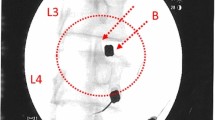

To provide a quantitative biomarker for IVD condition, DWI data analysis was performed in an imaging workstation (Advanced Workstation; GE Medical Systems). DWI visualizes diffusion of water molecules directly and ADC can be derived from a series of measurements with different diffusion sensitivity (b values) [30]. The ADC of the IVD was obtained from sagittal reformatted DWI images. An experienced radiologist (D-HH) evaluated IVD degeneration and quantitatively analyzed the images without knowledge of the clinical information. IVD degeneration was subjectively graded using Pfirrmann’s classification [29, 31]. The water content of the IVD was evaluated using ADC maps, which were generated from the series of DWI images. To quantify diffusions in the IVD, the ellipsoid region of interest (ROI, 50 mm2) was placed in the central half of the IVD. An elliptical ROI, on the middle section of sagittal fast spin echo (FSE) T2-weighted images (Fig. 1a), was manually drawn in the inner portion of each lumbar disc, indicating the regions of the NP. The ROIs were then copied to the ADC map (DWI with b factors of 0 (Fig. 1b) and 500 s/mm2 (Fig. 1c)) at the same level, and the ADC values (Fig. 1d) of the NP were calculated for analysis.

Measurement of the apparent diffusion coefficient (ADC) in lumbar degenerated discs. Mid-sagittal T2-weighted images were chosen and a region of interest (ROI, 50 mm2) placed in the central half of each disc. Sagittal fast spin echo (FSE) T2-weighted images (a) and diffusion-weighted images (DWI) with b factors of 0 (b) and 500 s/mm2 (c). ROI in the T2-weighted image copied to the ADC map from the DWI at the same level (d)